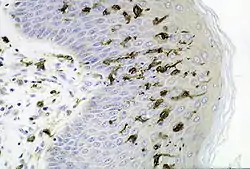

![]() Dendritic cells in skin | |

A dendritic cell